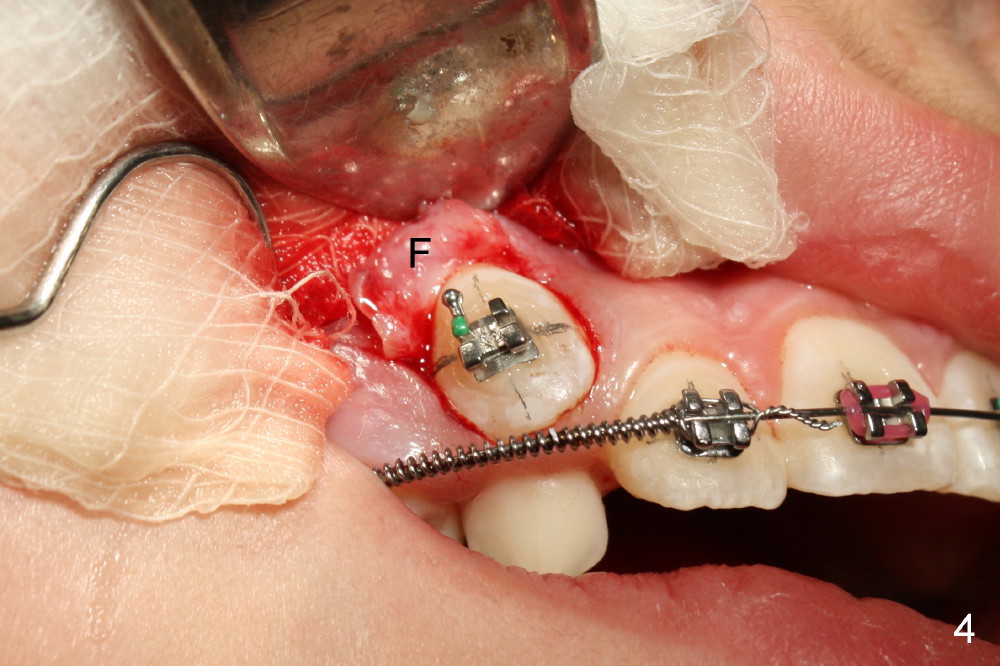

Two oblique incisions were made mesial and distal to UR3 (Fig.3). The mucoperiosteal flap (Fig.3 arrow; Fig.4 F) was raised and pushed apically for bracket placement. Following extraction of UR C, one-fourth inch elastics were placed between U3 and L3,4 (Fig.5,6). The patient was instructed to wear the elastics 24 hours per day. The upper wire is .018 ss with open coil springs, while lower .020.